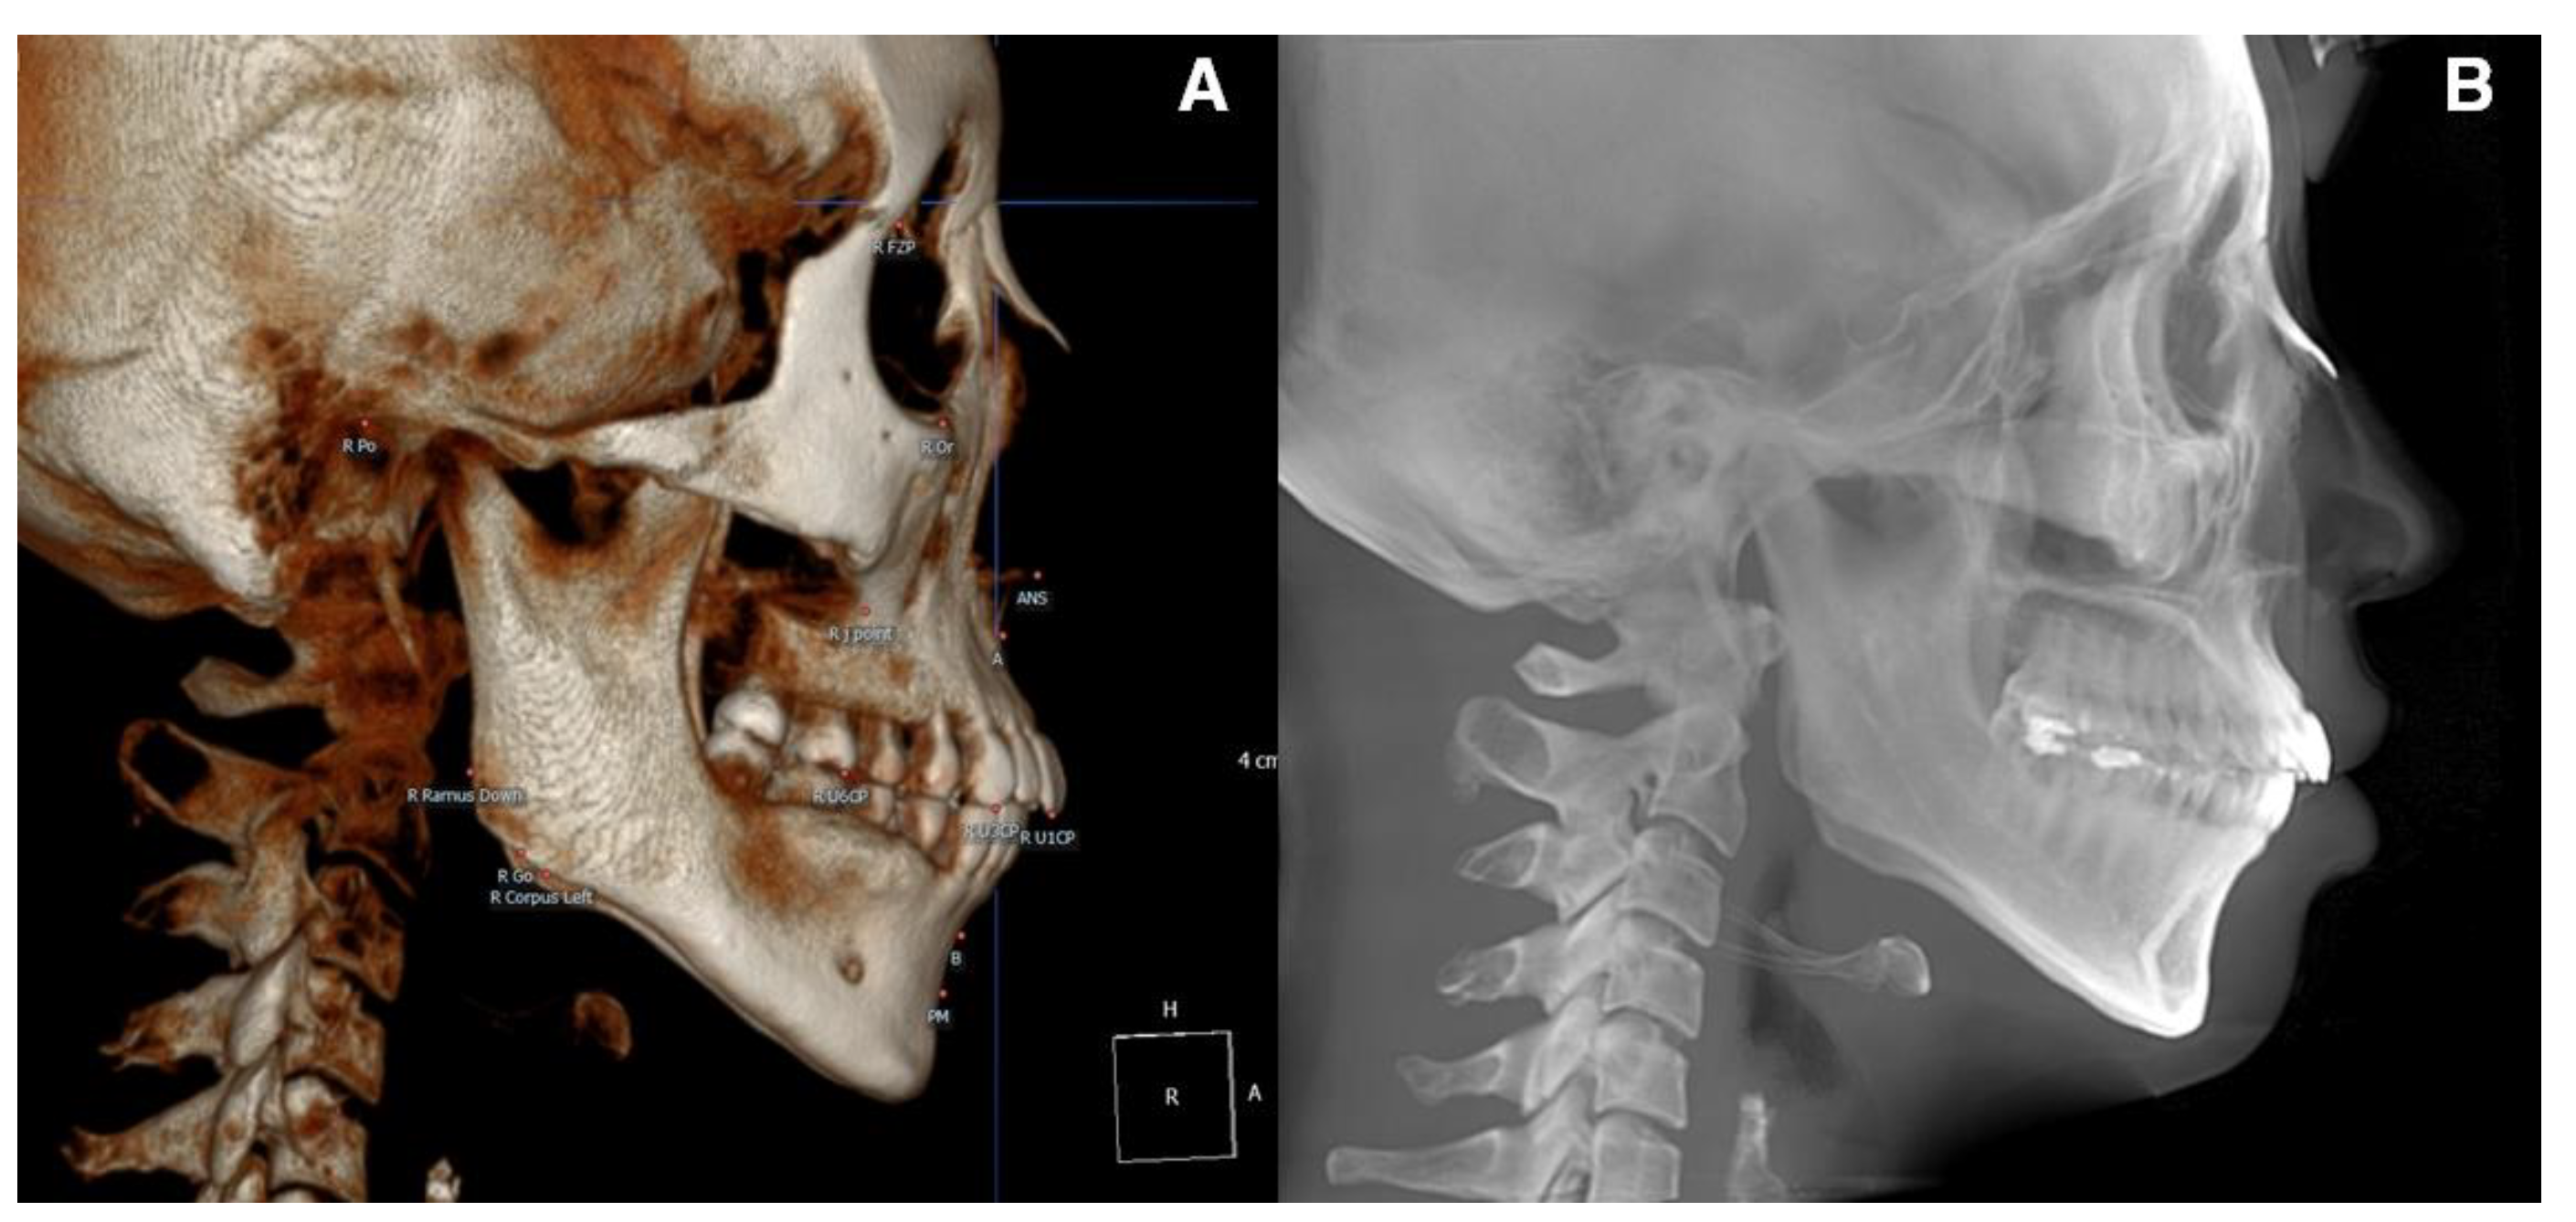

For the pre-treatment (T0) and post-treatment (T1) CBCT images, a coordinate system with the Frankfort horizontal plane parallel to the xy-plane, the line connecting the orbitale parallel to the x-axis, and the pogonion being set as the zero point was followed. CBCT cephalograms were synthesized from the reoriented CBCT data, and linear measurements were performed using the OnDemand3D software (Cybermed, Seoul, Korea) (Figure 1). To determine the total distance of the incisor movement, a vertical reference line (vert T) constructed through a stable craniofacial structure was used to measure the distance between the incisal tip and root apex between T0 and T1 (Figure 2).

Figure 1. (A), CBCT 3D image view. The image was oriented along the Frankfort horizontal plane in reference to the right porion, right orbitale, and left orbitale. (B), CBCT-synthesized lateral cephalogram was constructed in accordance with orientation.